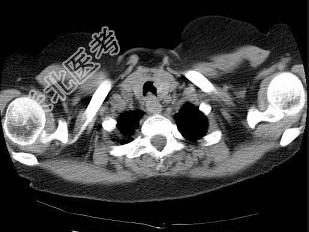

- 单项选择题男,68岁, 呼吸困难、轻度吞咽困难3月余,结合CT图像, 最可能的诊断是 ( )

A、气管乳头状瘤

B、气管脓肿

C、气管炎性假瘤

D、食管癌

E、甲状腺癌